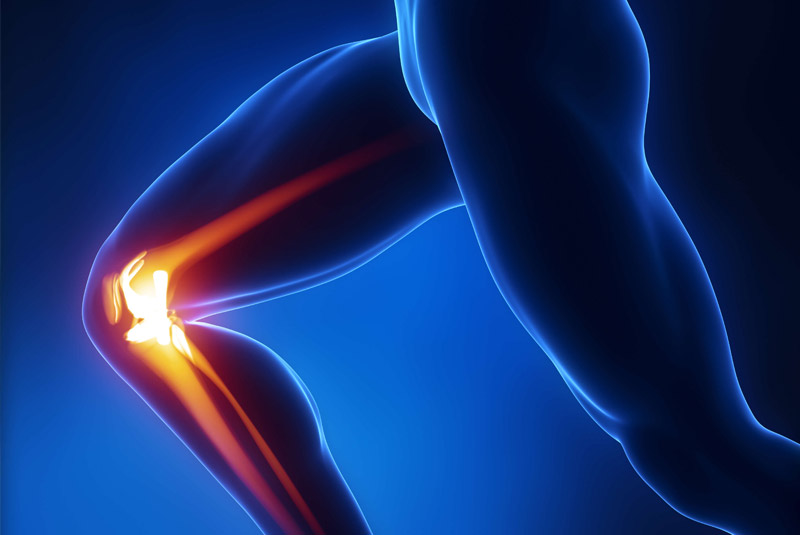

Έχει 5ετή μετεκπαίδευση και εργασία στο Ηνωμένο Βασίλειο ως ειδικός Ορθοπαιδικός Χειρουργός. Έχει εργαστεί στα Ορθοπαιδικά Τμήματα των Νοσοκομείων Southampton University Hospitals NHS Trust, Leeds Teaching Hospitals NHS Trust και στο Northampton General Hospital NHS Trust, με υποεξειδίκευση στη Χειρουργική Ώμου, Γόνατος, Ισχίου, Ποδοκνημικής & Άκρου Ποδός, Ώμου & Αγκώνος και Γενικού Τραύματος Ενηλίκων και Παίδων.

Κατά τη διάρκεια της εργασίας του στο Ηνωμένο Βασίλειο εκπαιδεύτηκε σε σύγχρονες τεχνικές Αρθροσκοπικής Χειρουργικής και Επανορθωτικής Χειρουργικής Ισχίου, Γόνατος και Ώμου. Επιπλέον έχει δώσει πολυάριθμες διαλέξεις και έχει εκπαιδεύσει νεότερους Ορθοπαιδικούς και φοιτητές Ιατρικής. Αξιοσημείωτο και πλούσιο είναι το επιστημονικό του έργο με συμμετοχή σε δεκάδες συνέδρια και σεμινάρια στην Ελλάδα και στο εξωτερικό και έχει πληθώρα προφορικών ανακοινώσεων και δημοσιεύσεων.